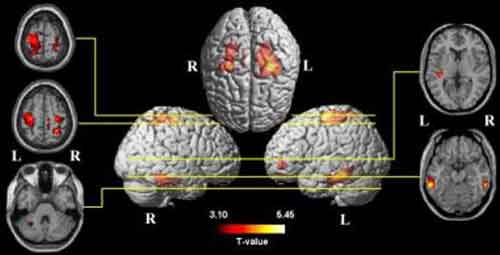

Tramite risonanza magnetica per immagini gli studiosi hanno scoperto che una maggiore spesa in termini di calorie era associata a maggiori quantita’ di materia grigia nei lobi frontali,temporali e parietali, incluso l’ippocampo, il cingolato posteriore e i gangli basali. Inoltre, c’era una forte associazione fra spesa energetica e maggior volume di materia grigia nei pazienti con lieve danneggiamento cognitivo.

“La materia grigia include neuroni che sottendono ai processi cognitivi e ai piu’ alti processi cerebrali. Le aree del cervello che beneficiano di uno stile di vita attivo solo quelle che consumano la maggior quantita’ di energia e sono molto sensibili al danneggiamento”, ha spiegato Cyrus Raji, che ha condotto la ricerca.